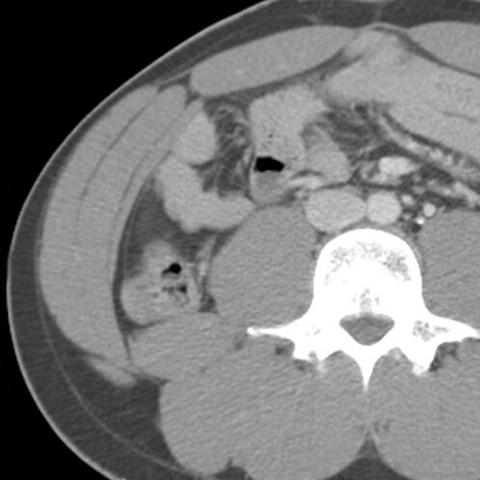

Abdominal Wall Muscles Normal Anatomy, Axial CT [3 of 9]